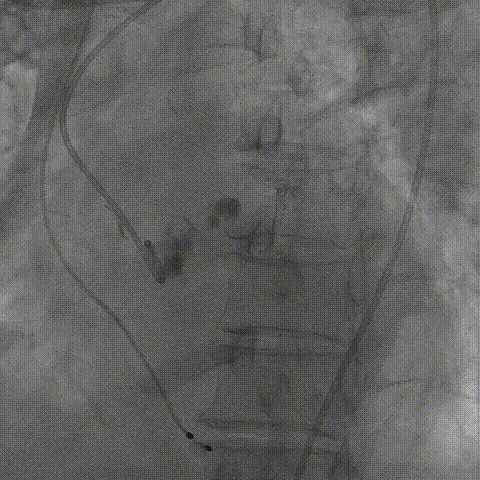

完全回收后瓣膜第三次释放

部分回收后瓣膜定位释放

球囊后扩张